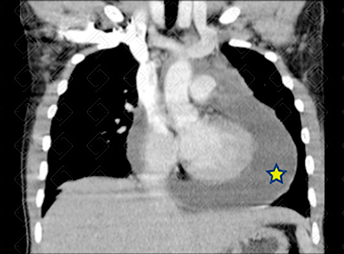

Texto alternativo para a imagem Figura 1. Créditos: Dra. Elazir Mota - Rio de Janeiro/RJ

Descrição das figuras 1 e 2: Tomografia computadorizada do tórax com contraste venoso. Volumoso derrame pericárdico (asteriscos). Paciento adulto jovem com febre e cansaço aos médios esforços. ADA do líquido positivo (+++). Diagnóstico de tuberculose confirmado.